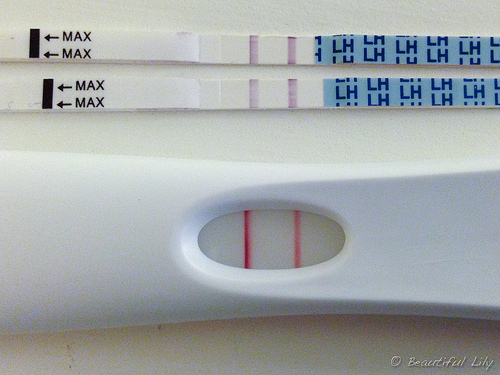

O teste de ovulação basicamente detecta um hormônio em abundância que faz o folículo romper e o óvulo sair para as trompas. O LH, hormônio luteinizante, em seus picos são capturados pelos anticorpos e reagentes existentes na tira de teste e fazem com que a linha de teste fique mais escura ou da mesma cor que a linha de controle. Caso a linha fique clara, então é sinal que o pico hormonal ainda não ocorreu.

O teste de farmácia complementa todos esses métodos de detecção. Os testes vendidos no Brasil têm cerca de cinco tiras e podem ser feitos durante todo o período fértil. Caso o teste não positive durante os dias que forem feitos, a mulher deve continuar a fazer mesmo que necessite de mais um kit de cinco testes. No entanto na grande maioria das vezes o teste chega a pegar o pico de LH sem maiores problemas. Esses episódios são isolados devido a ciclos com ovulação tardia.